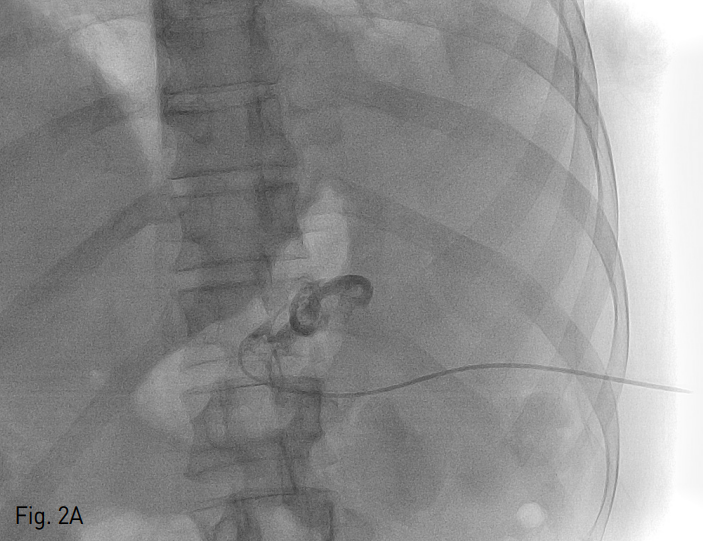

Fig. 2

Contrast accumulation through 5 Fr yellow sheath insertion after ultrasonograhy guided 22-gauge Chiba needle puncture (A). Up to 18 Fr rigid dilator was advanced coaxially over the 0.035 inch hydrophilic guide wire, progressively (B). 18 Fr Thal-Quick chest tube (Cook, Bloomington, IN, USA) was placed (C). The final catheter position can be confir med radiographically with contrast material (D).